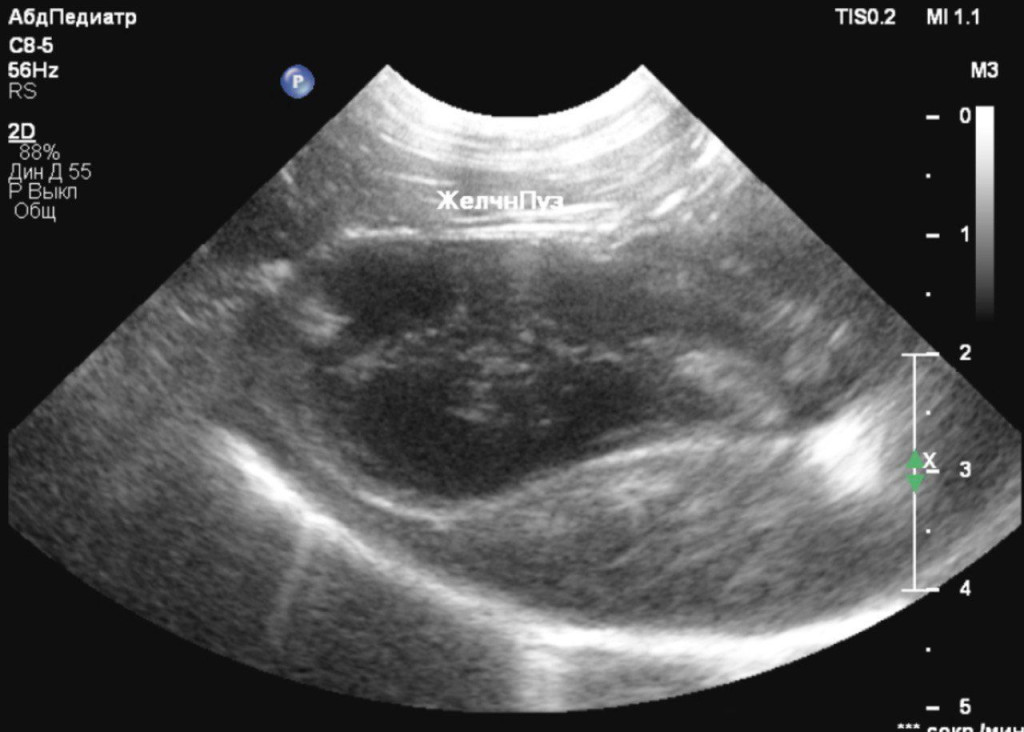

- пониженная эхогенность печени с однородной эхоструктурой и усиленным сосудистым рисунком, что может свидетельствовать о гепатопатии (рис. 2);

- каплевидная форма желчного пузыря с анэхогенным содержимым и скудным количеством гипоэхогенной взвеси (рис. 3);